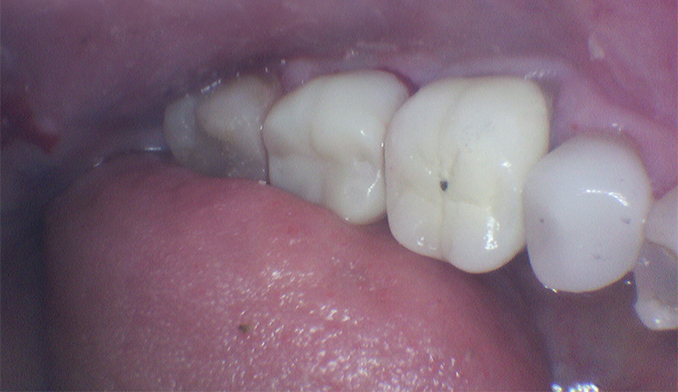

Same-Day Crown Replacement for Lower Molar

The patient’s old crown on the lower right molar came off and needed replacement. We created and cemented a new crown within a two-hour appointment, restoring the tooth’s function and appearance in one visit.